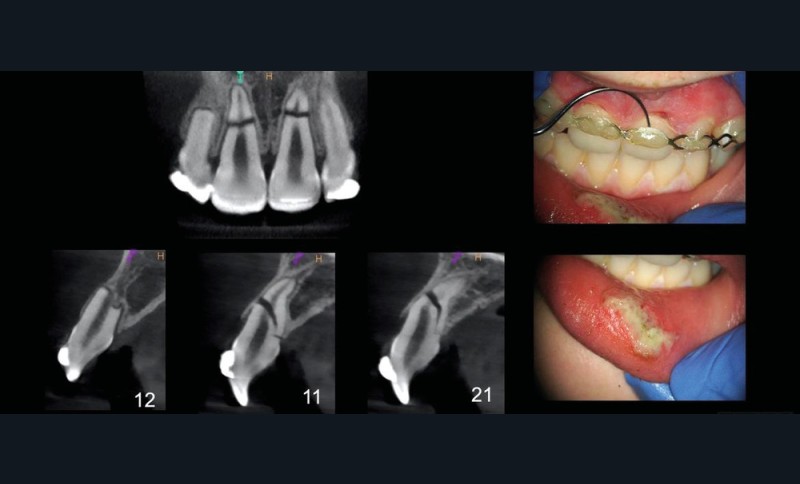

Les recommandations concernant la radiologie en traumatologie sont les suivantes : un cliché orthogonal par dent ayant subi le choc + une radiographie occlusale + une radiographie orthogonale de l’antagoniste. Par exemple, dans le cas d’un coup au niveau du bloc incisif antéro-supérieur, les 4 incisives sont susceptibles d’avoir été touchées, il faut alors réaliser une radiographie orthogonale de la 12, une de la 11, une de la 21, une de la 22, ainsi que le cliché occlusal et le cliché des incisives inférieures. La réalisation d’un CBCT est donc de plus en plus indiquée et doit répondre au principe ALARA. Ce cliché a-t-il une justification clinique et/ou thérapeutique [3] ?

La fig. 1 montre la situation clinique le jour du traumatisme. Les photographies et radiographies permettent d’observer des factures radiculaires des 4 incisives ainsi que, au minimum, la luxation de la 11. Deux fractures radiculaires horizontales importantes au niveau de la 11 et de la 21 sont notées. Une fracture moins marquée radiologiquement au niveau de la 22 et une résorption apicale au niveau de la 12 sont visibles. Cette dernière est probablement antérieure au traumatisme du jour. Le patient est d’abord pris en charge par un dentiste de garde qui pose une attelle (fig. 2). Il est ensuite référé pour une prise en charge en endodontie.

Lors de ce deuxième rendez-vous, un CBCT est prescrit et met en évidence l’étendue des fractures ainsi que le repositionnement inadéquat des deux fragments coronaires des dents 11 et 21 (fig. 3).